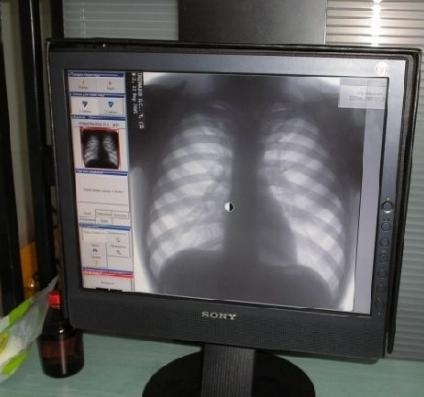

В декабре во 2-й городской больнице должен заработать цифровой флюорограф.

В декабре во 2-й городской больнице должен заработать цифровой флюорограф.